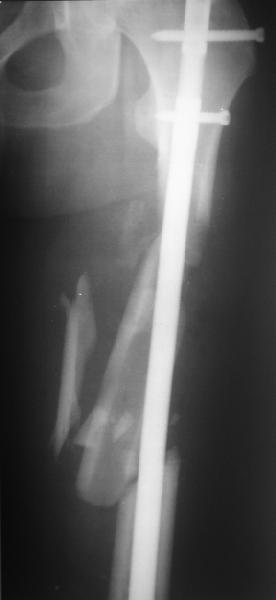

Мы бы не стали открывать, такие переломы срастаются, хотя бы и с краевым дефектом. То есть если удалять стержень потом, то сильно попозже обычного. В приложении пример. Сразу после операции и через 11 мес. Понятное дело, пациент к тому времени давно и не хромал, и функция колена была полная.